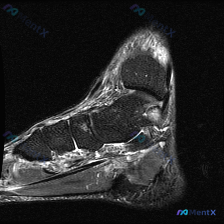

看到一个很典型的足部MRI读片病例,整理了影像特征和完整的分析思路,分享给大家一起讨论。 一、病例影像基本信息 这是一张足部冠状位液体敏感序列(T2-FS/STIR)MRI,图像对比度良好,无明显伪影,主要显示后足跟骨、距骨及踝关节周边软组织。 二、核心影像发现 1. 骨骼:跟骨信号均匀,未见皮质中...